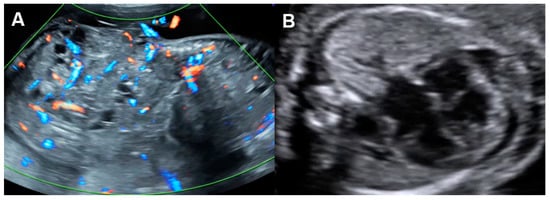

| Parameters | Abnormal Changes | Interpretation |

|---|---|---|

| Dimension | ||

| Cardiothoracic area ratio | Increased >35% | Cardiac enlargement |

| Cardiothoracic diameter ratio | Increased >95th centile | Cardiac enlargement |

| Inflow characteristics | ||

| Filling time fraction | Decreased | Diastolic dysfunction |

| E/A ratio | Monophasic | Diastolic dysfunction |

| Decreased | Diastolic dysfunction | |

| Increased | Volume loading/External compression | |

| Venous PW Doppler | ||

| Inferior vena cava | Reversed A-wave >20 cm/s | Diastolic dysfunction /increased venous pressure |

| Decreased S-wave | Tricuspid regurgitation | |

| Ductus venosus | Absent or reversed A-wave | Diastolic dysfunction/increased venous pressure |

| Performance | ||

| Shortening fraction | Decreased (<28%) | Systolic dysfunction |

| Increased | Reduced afterload/increased contractility | |

| Ejection fraction | Decreased <50%) | Systolic dysfunction |

| Cardiac output (Stroke volume) | Decreased (Z < −2) | Systolic dysfunction/poor filling |

| Increased (Z > +2) | Reduced afterload/volume load | |

| Tei index | Increased > 0.50 | Global cardiac dysfunction |

| ICT: 28 (22–33) ms | Prolonged | Systolic dysfunction |

| IRT: 34 (26-41) ms | Prolonged | Diastolic dysfunction |

| Systolic strain/Strain rate | Increased | Reduced afterload |

| Decreased | Reduced contractility | |

| E/Vp (Color M-mode) | Increased | Diastolic dysfunction |

| Normal | −1 Point | −2 Points | |

|---|---|---|---|

| Hydropic signs | Absence of effusion | Abdominal or pleural, or pericardial effusion | Skin edema |

| Venous Doppler (umbilical vein: UV & ductus venosus: DV | Normal Doppler UV ![]() DV ![]() | Reversed ductus venosus flow UV ![]() DV ![]() | Pulsatile flow in the umbilical vein UV ![]() |

| Heart size (Cardio-thoracic ratio) | ≤35% | 35–50% | >50% or <20% |

| Cardiac function | Normal function | Holosystolic TR, or ventricular shortening fraction < 28% | Holosystolic MR or TR dP/dt < 400, or monophasic inflow |

| Arterial Doppler (umbilical artery) | Normal Doppler![]() | Absent end-diastolic flow![]() | Reversed end-diastolic flow![]() |